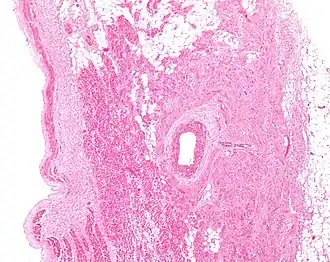

Microanatomy

The cells of the SA node are spread out within a mesh of connective tissue, containing nerves, blood vessels, collagen and fat. Immediately surrounding the SA node cells are paranodal cells.[2] These cells have structures intermediate between that of the SA node cells and the rest of the atrium.[6] The connective tissue, along with the paranodal cells, insulate the SA node from the rest of the atrium, preventing the electrical activity of the atrial cells from affecting the SA node cells.[2] The SA node cells are smaller and paler than the surrounding atrial cells, with the average cell being around 8 micrometers in diameter and 20-30 micrometers in length (1 micrometer= 0.000001 meter).[7] Unlike the atrial cells, SA node cells contain fewer mitochondria and myofibers, as well as a smaller sarcoplasmic reticulum. This means that the SA node cells are less equipped to contract compared to the atrial and ventricular cells.[8]

Action potentials pass from one cardiac cell to the next through pores known as gap junctions. These gap junctions are made of proteins called connexins. There are fewer gap junctions within the SA node and they are smaller in size. This is again important in insulating the SA node from the surrounding atrial cells.[2][8]